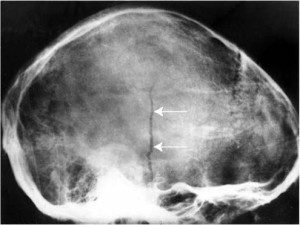

Линейные переломы именуются так, потому что повреждения похожи на тонкую линию. При этом отсутствуют смещения фрагментов костной ткани. Линейные повреждения темени не очень опасны сами по себе. Однако они могут привести к появлению эпидуральных гематом и повреждению оболочечных артерий.